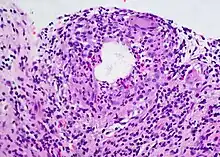

Diagnosis

A chalazion or meibomian cyst can sometimes be mistaken for a stye.